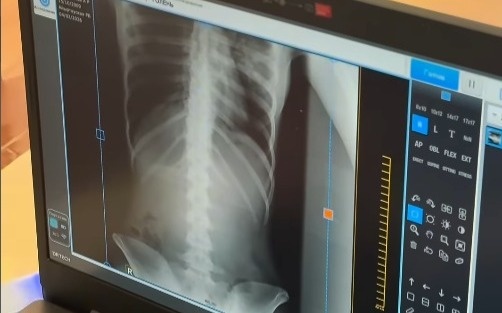

Фото: видеодан алынған скрин